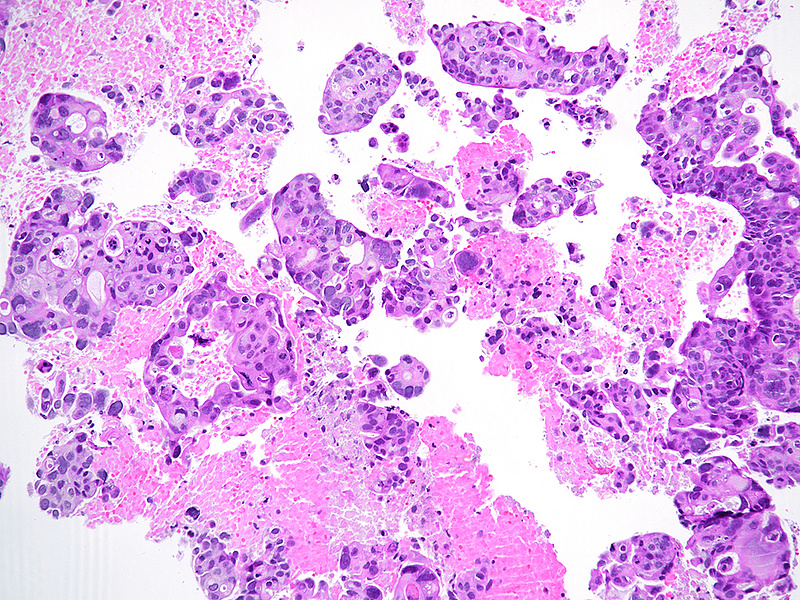

The well-sampled biopsy showed fragments of a necrotising carcinoma, arranged in isolated cells, small aggregates of cells and poorly formed glandular structures (Panels A-B). The tumour cells demonstrated abundant eosinophilic cytoplasm and severely pleomorphic, hyperchromatic nuclei with distinct nucleoli. Brisk mitotic activity was noted (Panel C). Within some clusters, the neoplastic cells had a more polygonal appearance, with intercellular desmosomes, more basophilic cytoplasm and evidence of dyskeratosis (Panels D-E).